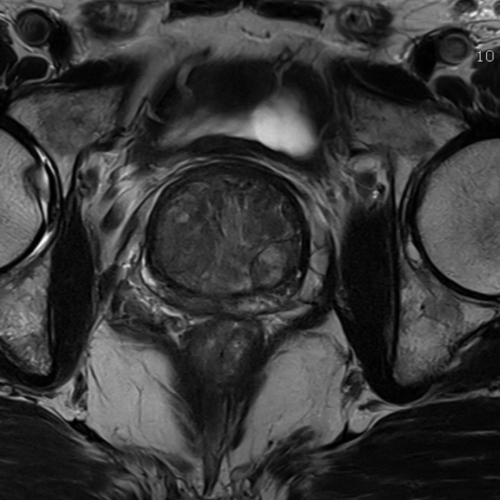

Cet examen est réalisé pour analyser la prostate, les vésicules séminales, les ganglions. Il est réalisé pour le dépistage du cancer de la prostate après dosage du PSA si celui ci augmente au dessus de 4 ng/mL.

Cette examen permets de diagnostiquer:

- les cancers de la prostate

- les infections de la prostate (prostatite)

- les abcès de la prostate

- l’hypertrophie adénomateuse de la prostate

Le Score PIRADS est utilisé pour classer l’examen . Des biopsies échoguidées de prostate sont réalisées en cas de score PIRADS 4 ou 5